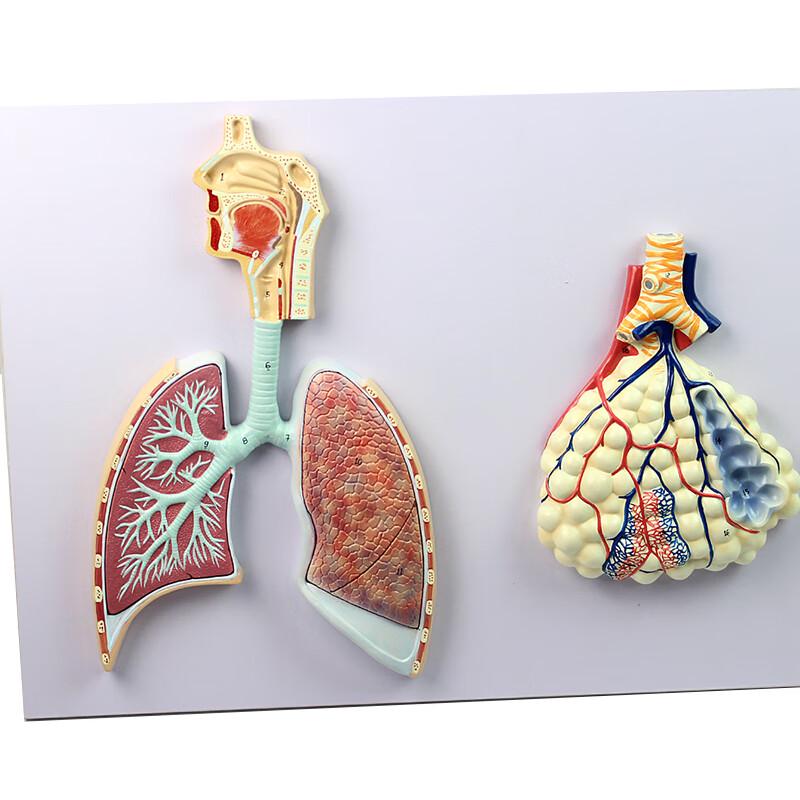

Human Respiratory System Anatomy Model

4d Anatomical Assembly Model of Human Organs Respiratory System Medical Anatomy

M17F Life Size Human Lung Model Anatomical Respiratory System Anatomy Teaching Tool

Human Larynx/Heart/Lung Anatomical Model Medical Model Pulmonary Anatomy Model Respiratory System Model Teaching Supplies

Lung Respiratory Anatomy Model Teaching System Human Display model School Lungs Anatomical Heart Educational Nasal Toy

Lung Respiratory Anatomy Model Teaching System Human Display model School Lungs Anatomical Heart Educational Nasal Toy

Lung Respiratory Anatomy Model Teaching System Human Display model School Lungs Anatomical Heart Educational Nasal Toy

Lung Respiratory Anatomy Model Teaching System Human Display model School Lungs Anatomical Heart Educational Nasal Toy

PVC Respiratory System Model Lifelike Teaching Aid for Medical Schools Anatomy Education Practical Human Lung Display Tool

Diseased Human Lung Structure Respiratory System Model for Anatomical Study Display Teach Anatomy Medical Supply and Equipment